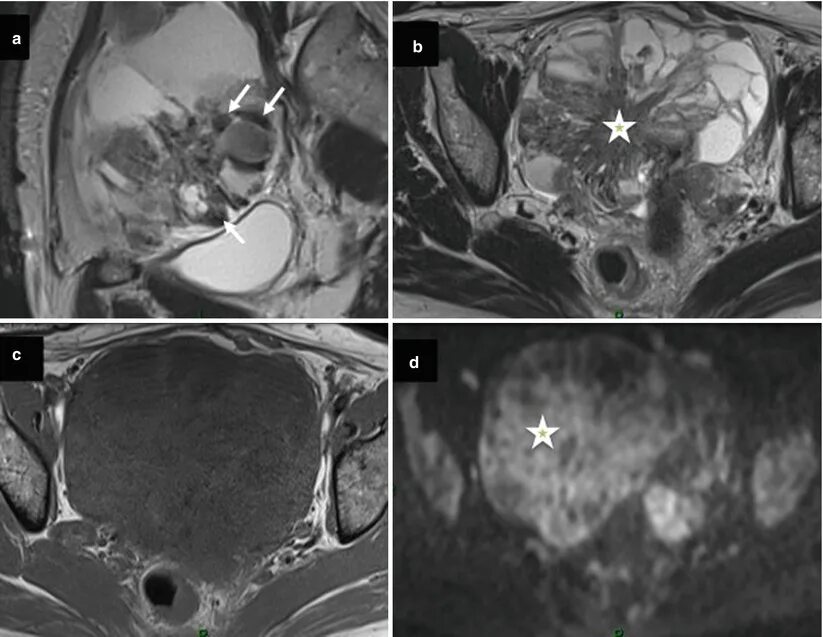

Метастазы в простате